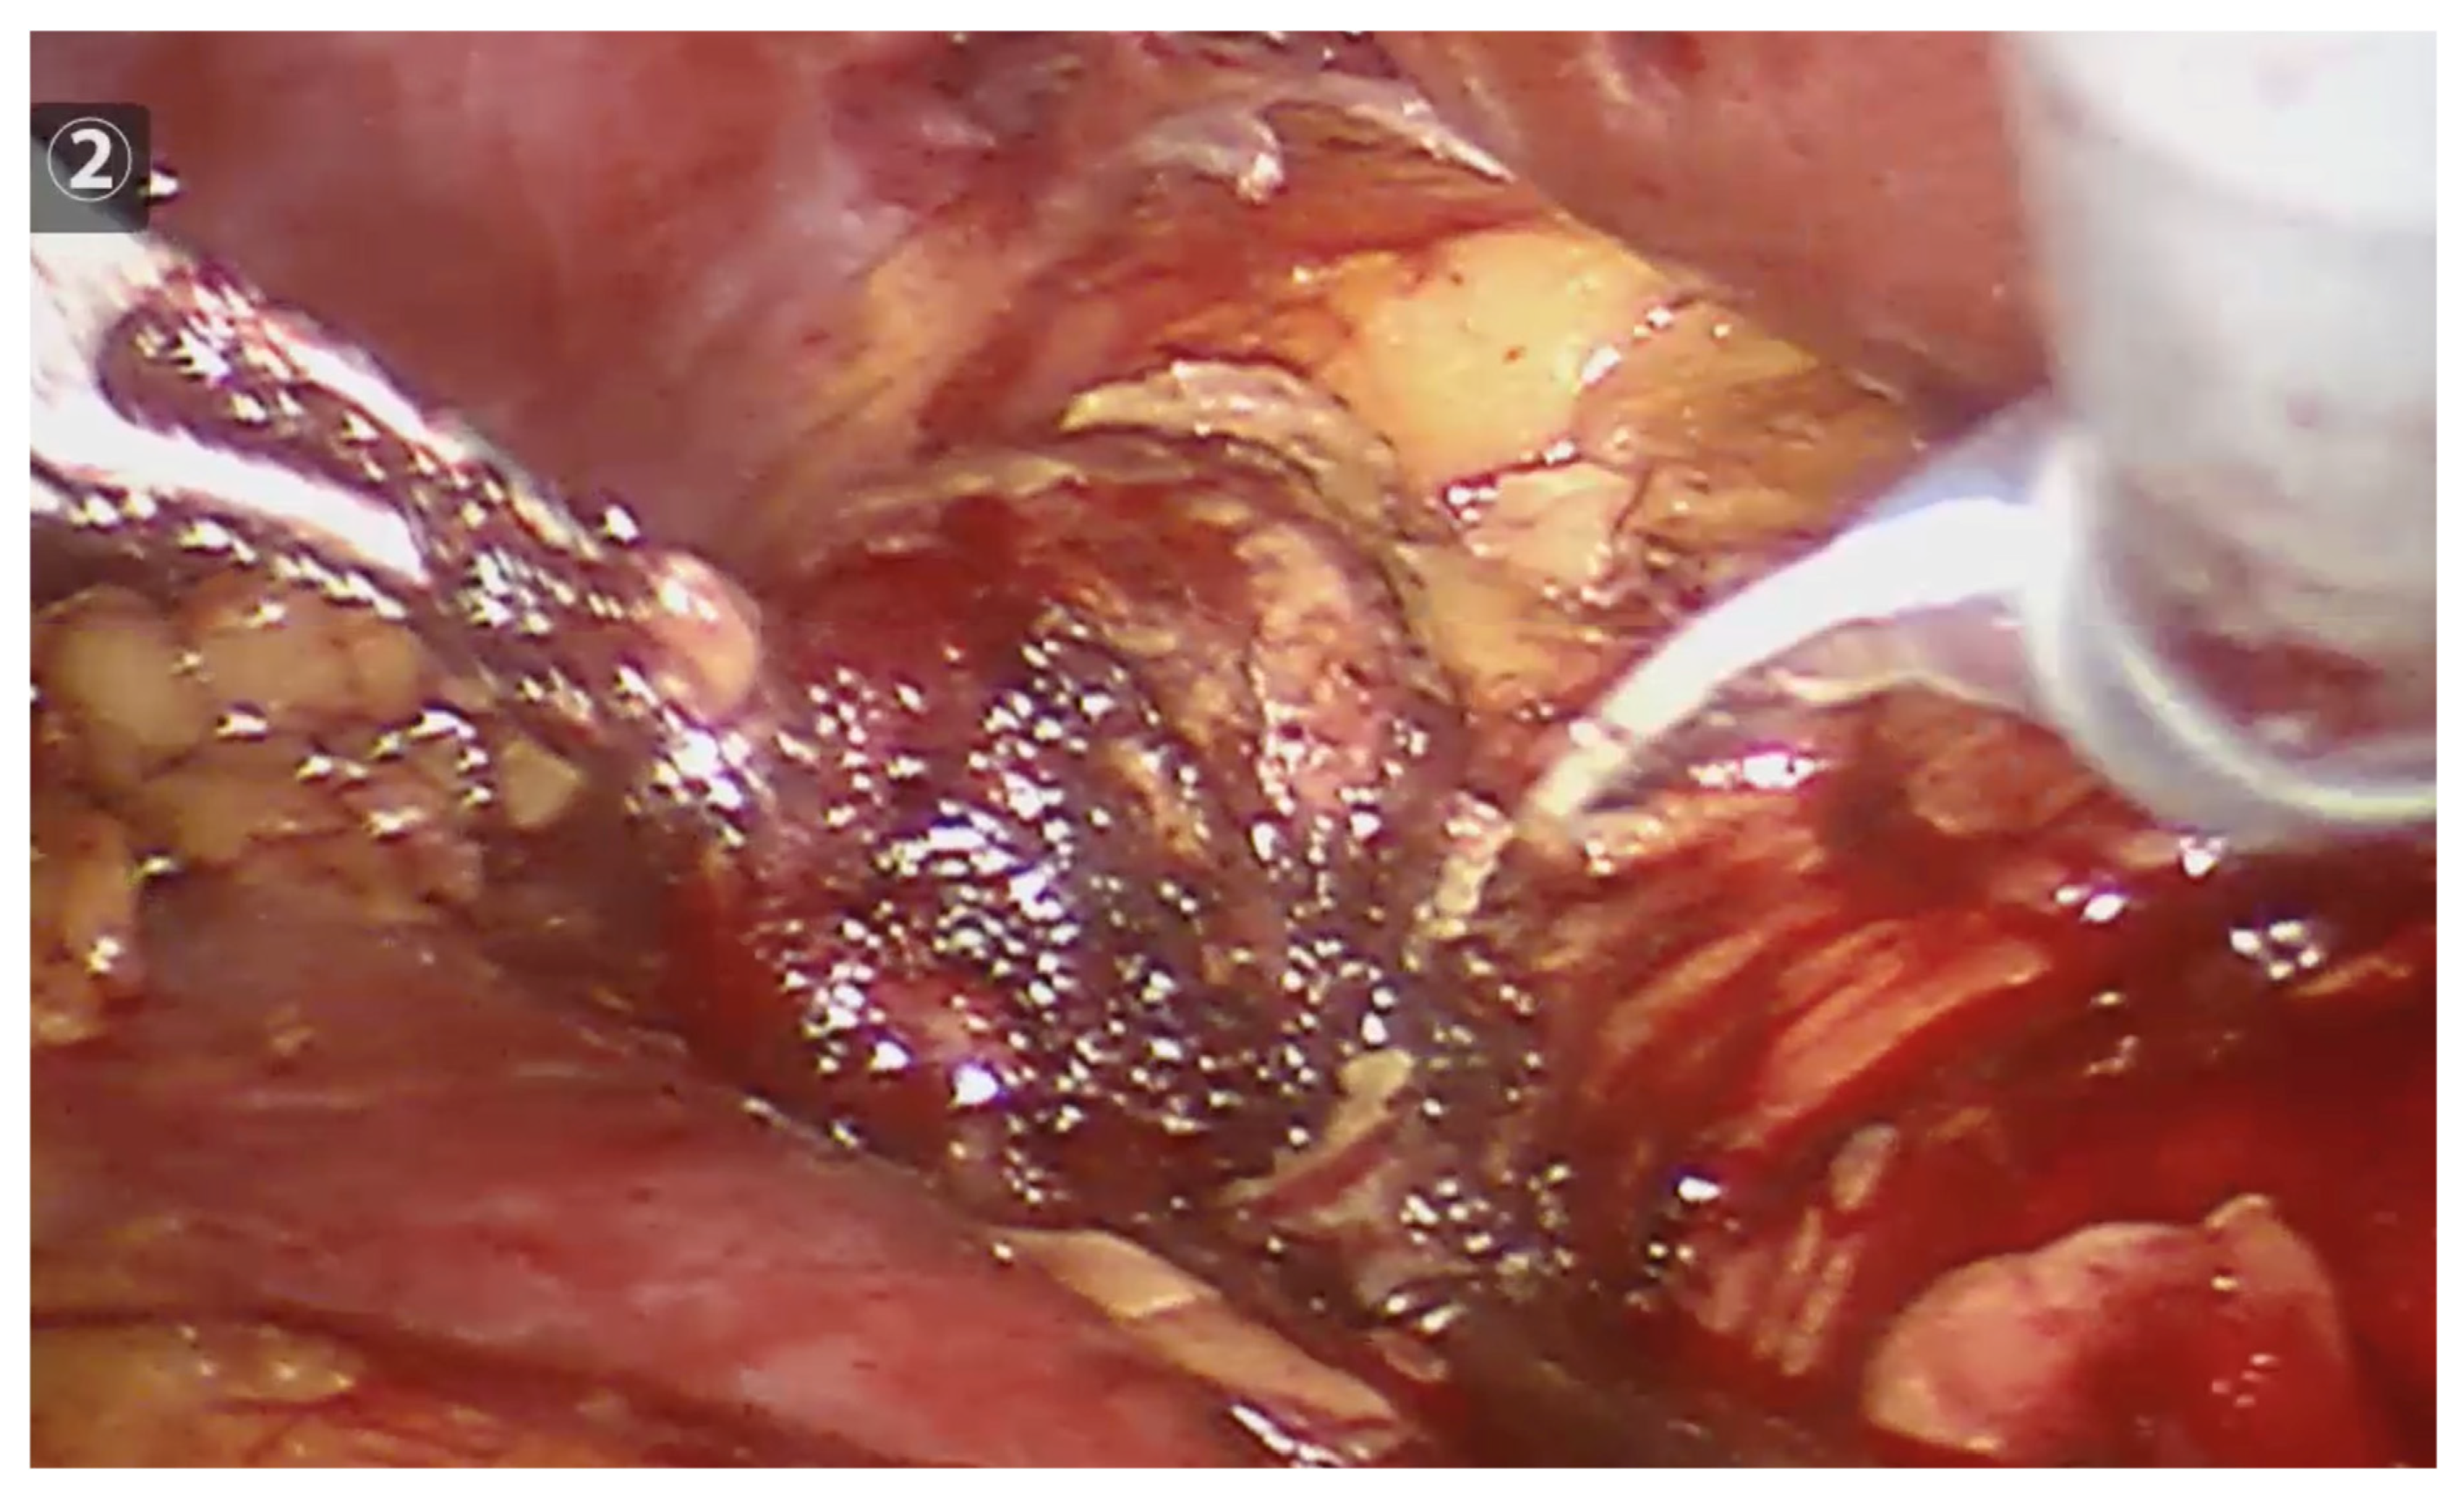

The needle length and diameter were selected based on the size of the tumor and its proximity to or distance from the abdominal wall. The radiofrequency needles had diameters ranging from 1.5 to 3 cm and lengths between 30 and 35 cm. Peri-tumoral radiofrequency needle punctures were performed until maximum impedance was reached, in larger lesions (600–700 kHz), or up to 300–400 kHz, in smaller lesions. The puncture was made 3 mm from the visible tumor edge and 1 to 1.5 cm deep. The needle was not removed until no further evidence of bleeding was observed. The number of punctures varied, depending on the size of the lesion, with all punctures performed peri-tumorally at the border between the tumor tissue and healthy kidney tissue (See Figure 2). After performing radiofrequency along the entire edge of the lesion, a necrotic halo is demarcated, which facilitates its resection (See Figure 3).

Figure 3.

Robotic tumor resection, after completing the peritumoral radiofrequency, clearly shows a necrotic halo, which will guide the resection.